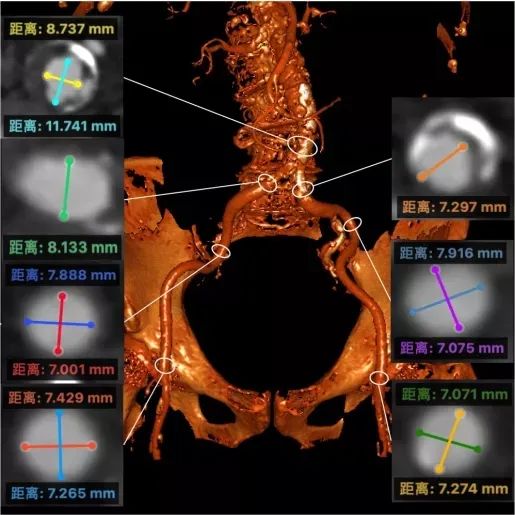

冠状动脉CT检查:右髂动脉支架术后闭塞。

主动脉瓣环:平均直径24.6 mm、周长75.6 mm

左室流出道:最大直径25.5 mm、周长80.3 mm

左、右冠脉高度:分别为17.2 mm、15.1 mm,且双侧冠脉开口均有钙化

窦管交界处:平均直径29.7 mm、周长93.3 mm

瓣环成角:54°

双侧股动脉入路:均在7 mm以上

总钙化量:968 mm²

根据影像学检查结果,最终决定采用右股动脉为主入路,选择22 mm预扩球囊及植入VitaFlow TAV27 mm生物瓣膜。